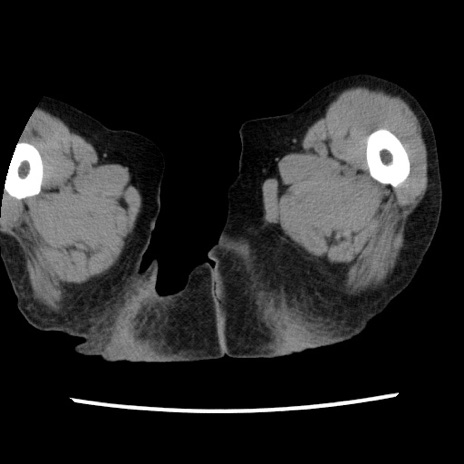

冠状断像

矢状断像